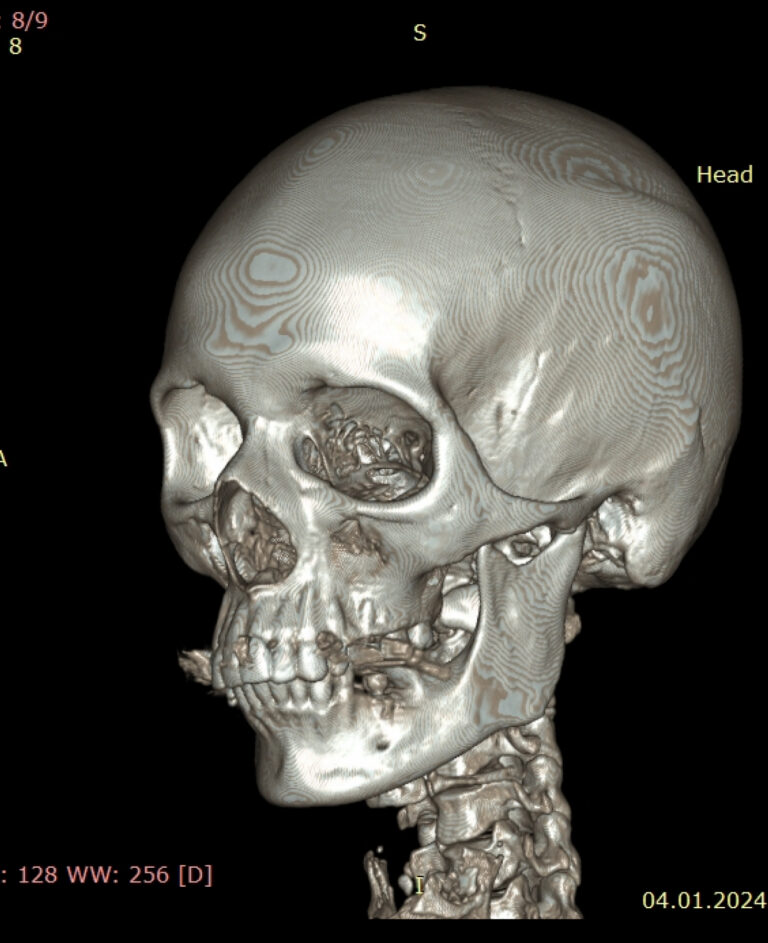

Мультиспиральная дентальная компьютерная томография (МДКТ или, как ее еще называют, КТ зубов) – это современный высокоточный метод лучевой диагностики, с помощью которого получают объемные цифровые изображения всей зубочелюстной системы. В основе метода лежит применение рентгеновского излучения и последующая цифровая обработка полученных данных специальными компьютерными программами.

Мультиспиральный томограф выполняет послойное сканирование области верхней и нижней челюстей с помощью рентгеновских лучей, а затем, используя компьютерную обработку данных, создает 3D-модели исследуемой зоны. Современные модели томографов проводят круговое сканирование по спирали, делая срезовые снимки на расстоянии 0,5 мм друг от друга. Затем на основе этих данных реконструируются детальные изображения челюстно-лицевой области в трехмерном формате.

- Широкие возможности диагностики. На трехмерных изображениях можно увидеть в целом верхнюю и нижнюю челюсть, включая гайморовы пазухи, височно-нижнечелюстные суставы. Помимо костной ткани при проведении КТ можно оценить состояние окружающих мягких тканей. Это бывает особенно важно при выборе оптимального способа протезирования и имплантации, при подозрении на опухолевые процессы, при планировании оперативного вмешательства.

Исследование занимает всего пару минут. Данные, полученные при сканировании, проходят цифровую обработку и выводятся на монитор компьютера в виде 3D-изображений. Врач-рентгенолог внимательно анализирует данные и выдает заключение.

Высокая информативность исследования за счет детальных снимков и наглядных пространственных 3D-реконструкций позволяет увидеть то, что недоступно для визуального осмотра и обычного рентгеновского обследования.